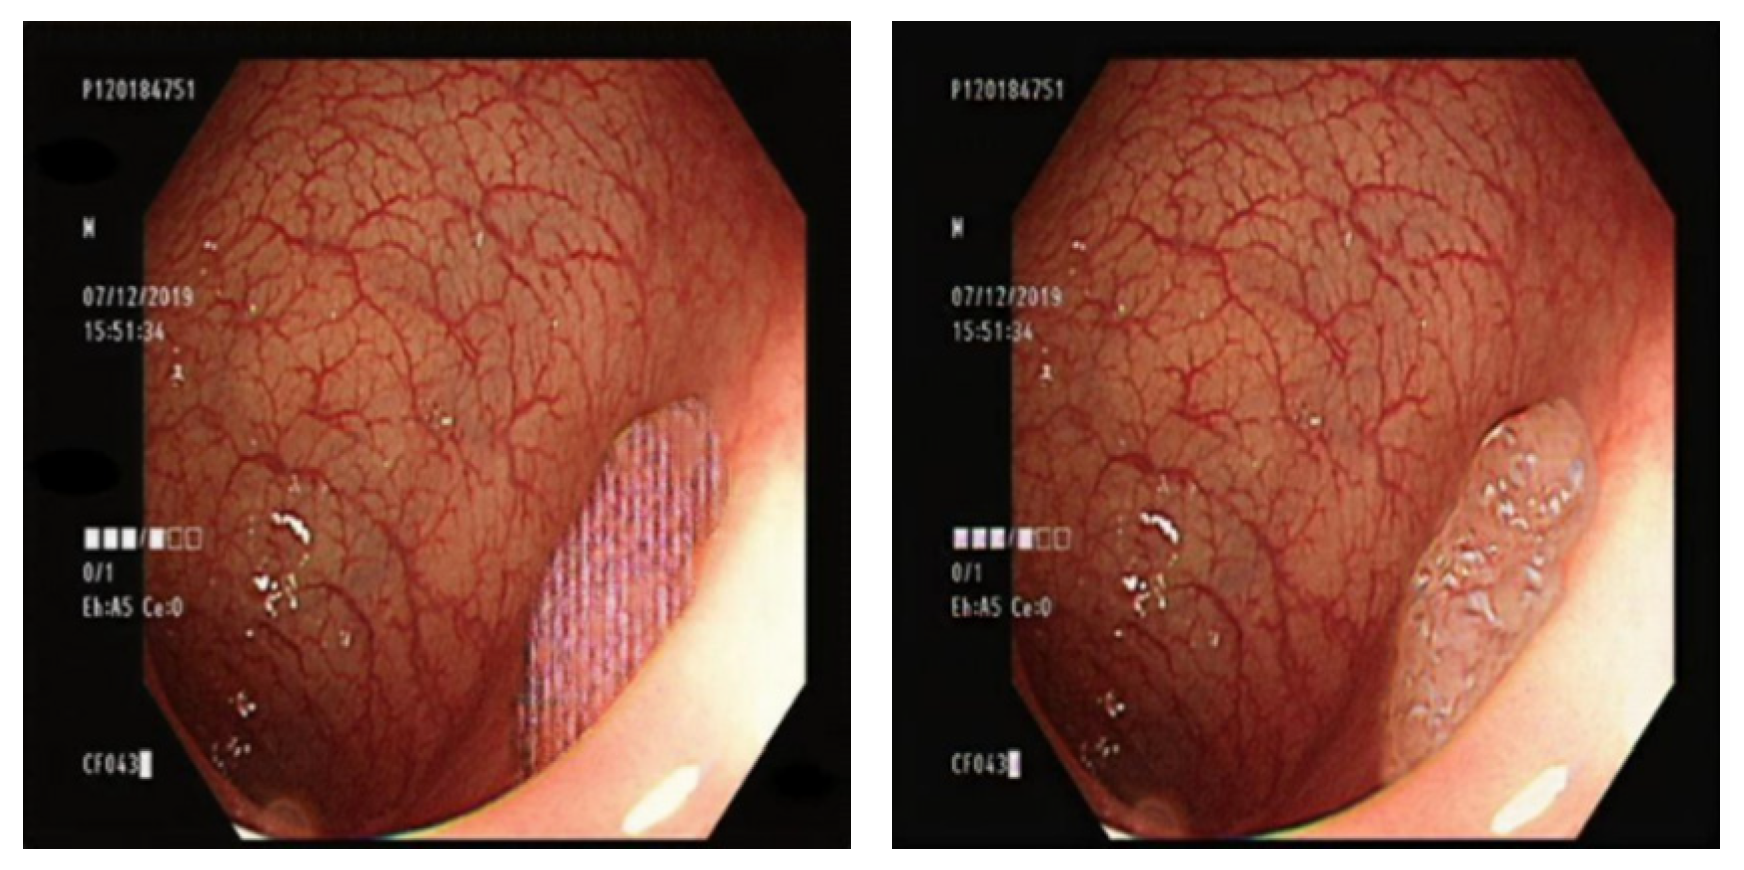

4.1. Comparison of GAN-Generated Images

3.7. Comparison of GAN Output

4.2. Comparison of YOLO Using Different Datasets